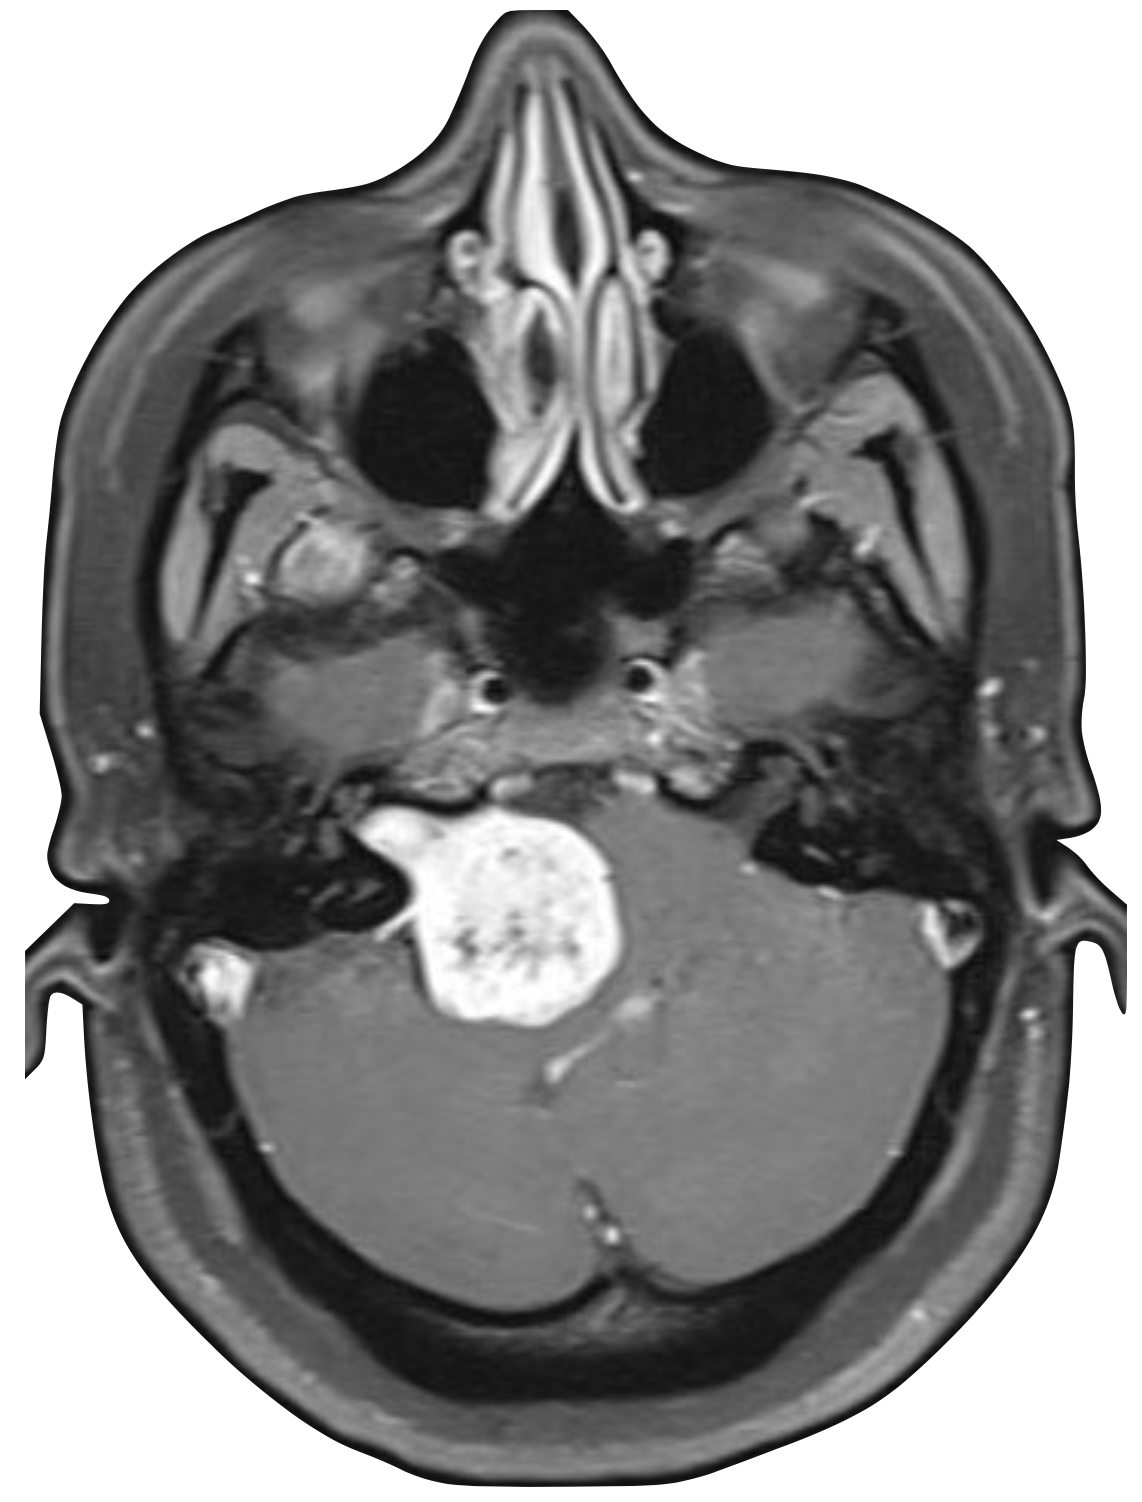

Advanced otology encompasses complex ear and skull base conditions requiring specialized surgical care. We offer cochlear implants and bone conduction implants for hearing loss, treat acoustic neuroma and temporal bone tumors, and perform stapes surgery for otosclerosis. Our team also manages cholesteatoma, superior canal dehiscence, and other advanced ear conditions. Select a topic below to learn more.